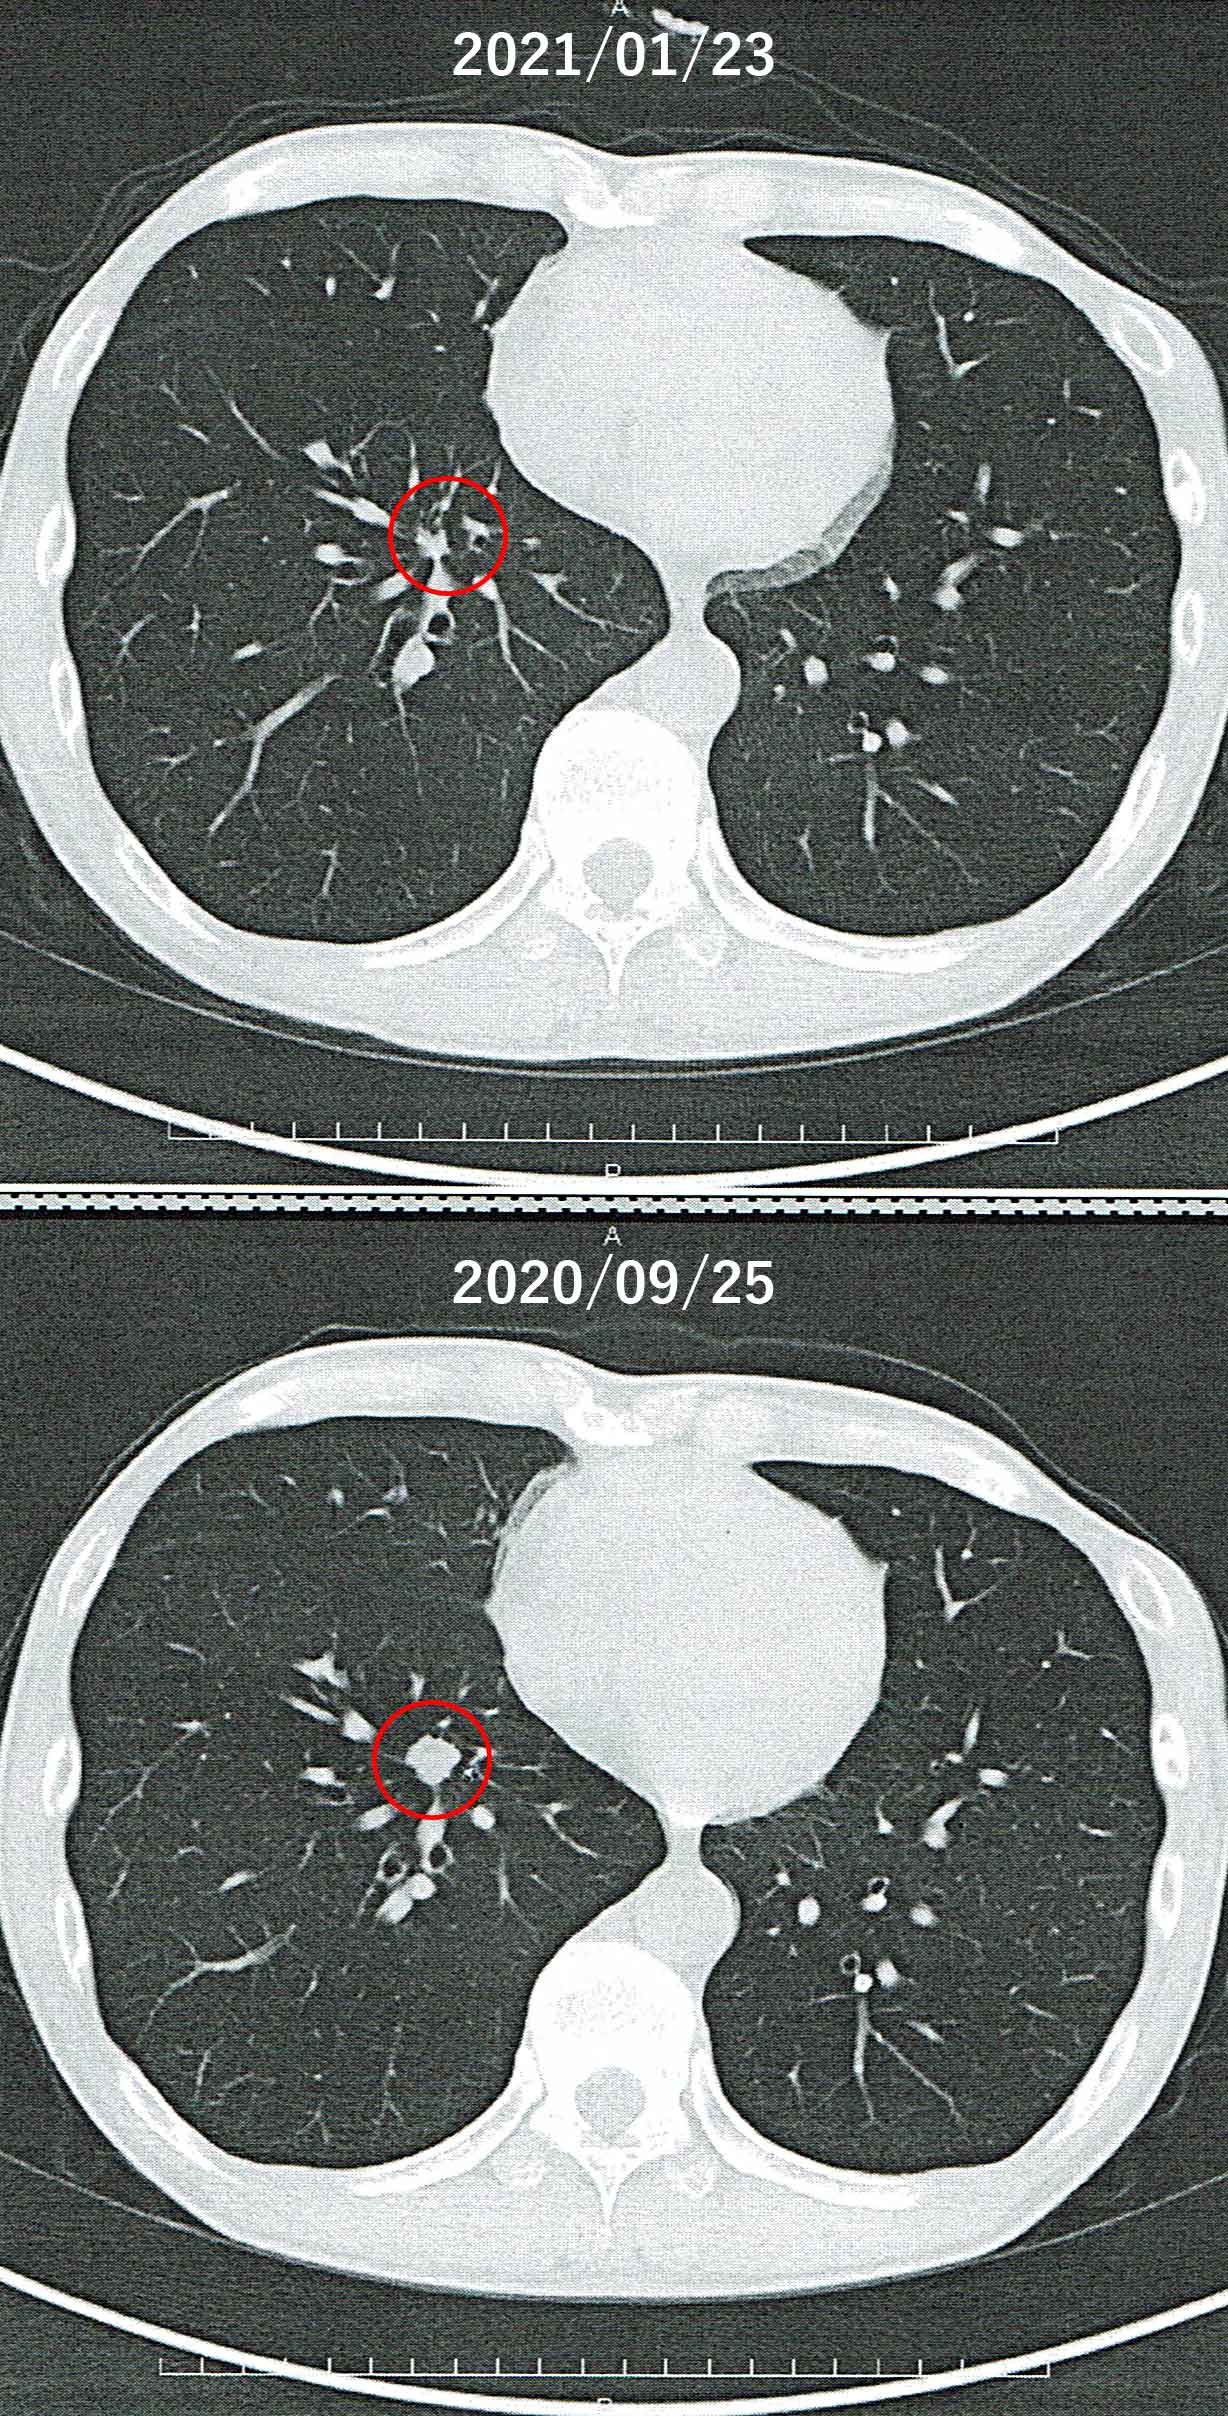

東邦大学医療センター大森病院にて、呼吸器内科を受診し、土曜日に実施した血液検査、尿検査、胸部CT撮影(造影剤無し)の結果を聞きました。 血液検査・尿検査の結果は異常無しです。 問題は胸部CT撮影(造影剤無し)の結果です。 サイバーナイフ治療の結果、右肺の腫瘍はだいぶ小さくなりました。残っているのは「やけどの痕のようなもので、死んでいるはず」とのことです。サイバーナイフの治療は成功と言えるようです。

これで、しばらくは落ち着けるかと思いましたが、残念ながら左肺の一昨年末に手術したあたりに再発が見つかりました。昨年9月に撮ったCTを改めて見ると、このころから薄く見られるようになり、今回のCTでは、それがはっきりとして、かつ、大きくなっています。成長も速そうです。肺葉全体を取らなかったためでしょうか。

他の臓器に転移している可能性がありますので、PETを行うことになりました。ここで気になるのは、2019年7月13日に実施したPETで、がん細胞と思われるところも含めてどこも光らなかったことです。このとき、実は、PETを実施すると決まってからPETを実施するまでの2週間弱、毎日熱い風呂に10分間浸かるということを行っていました。それがPETが光らなかった原因かどうかを切り分けるため、今回も同じことをやってみることにしました。 |